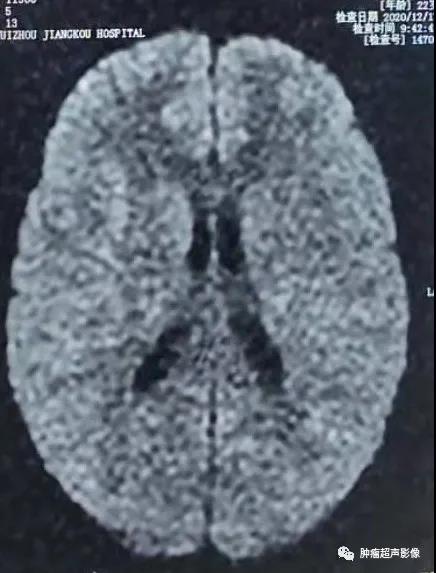

MR表现为两侧额枕叶皮层及皮层下多发结节或皮层增厚、脑回肥厚,FLAIR信号增高。

头颅CT示两侧侧脑室下多发小结节状钙化,增强MR示室管膜下结节明显强化。